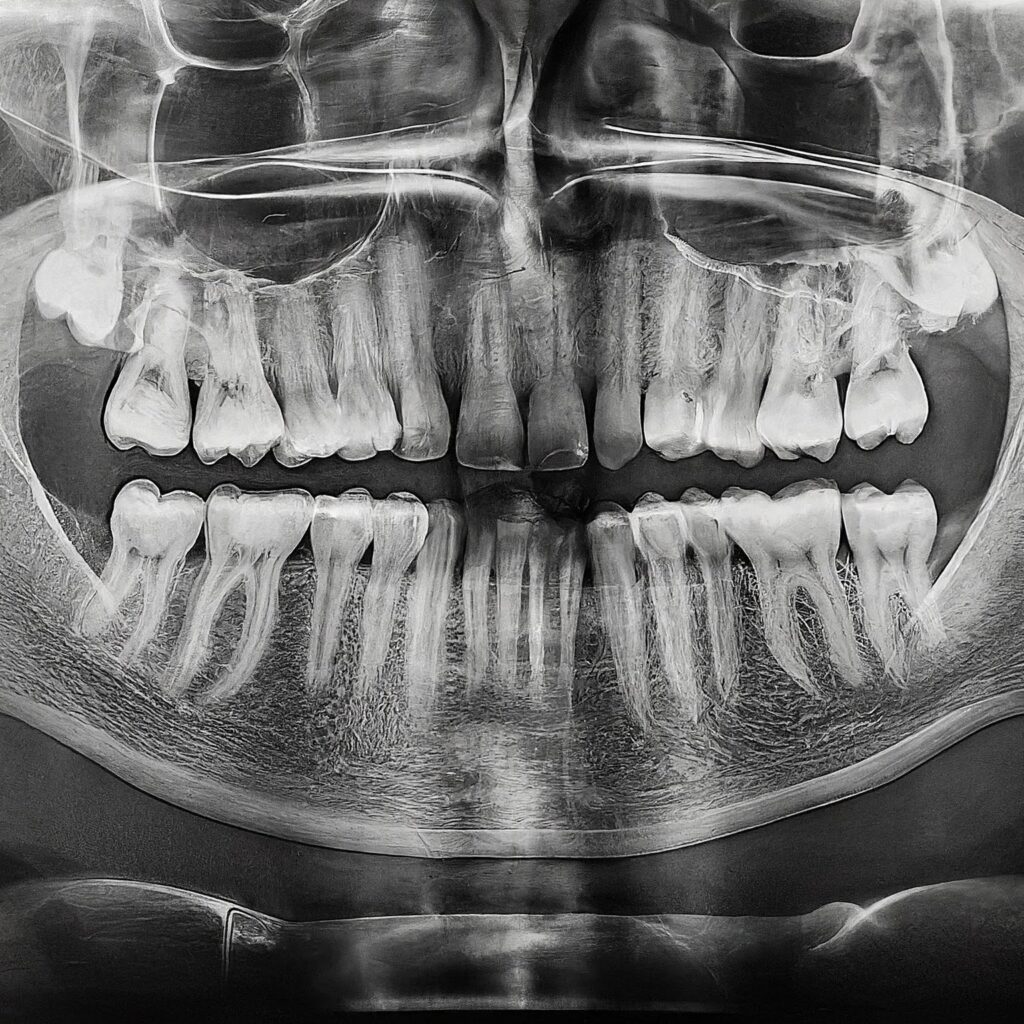

image_fx_dental_xray (2) - New Smile Clinic Lubumbashi

TRAITEMENT DE LA PARODONTITE

Les causes et les conséquences

Les gencives et l’os sain de la mâchoire tiennent les dents fermement en place. Le point d’attachement des dents aux gencives se trouve juste sous le rebord des gencives. C’est là que survient les maladies de gencive.

L’infection peut débuter par l’accumulation de la plaque qui se forme à la jonction des dents et des gencives. Si la plaque n’est pas enlevée avec la brosse à dents et la soie dentaire, elle durcit et se transforme en tartre. De là, diverses maladies pourraient apparaître.

La meilleure façon de soigner les maladies de gencive, c’est de les éviter. Pour protéger votre santé buccodentaire, brossez-vous les dents au moins deux fois par jour, passez la soie dentaire au moins une fois par jour et consultez votre dentiste régulièrement pour des examens dentaires.